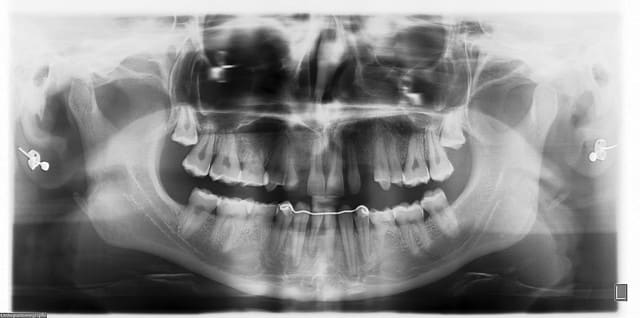

-patiente 22 ans

-10 agénésies (15, 13, 12, 23, 38, 35, 31, 41, 45, 48)

-ODF réalisé par mon père à son adolescence pour "limiter" au tant que faire se peut les préjudices esthétiques...

-53 encore présente mais en phase terminale

-microdonties

-demande esthétique pour le secteur antérieur supérieur pour le moment...

jolie la pano.. quelle marque / modèle?

pano instrumentaruim OP 200D